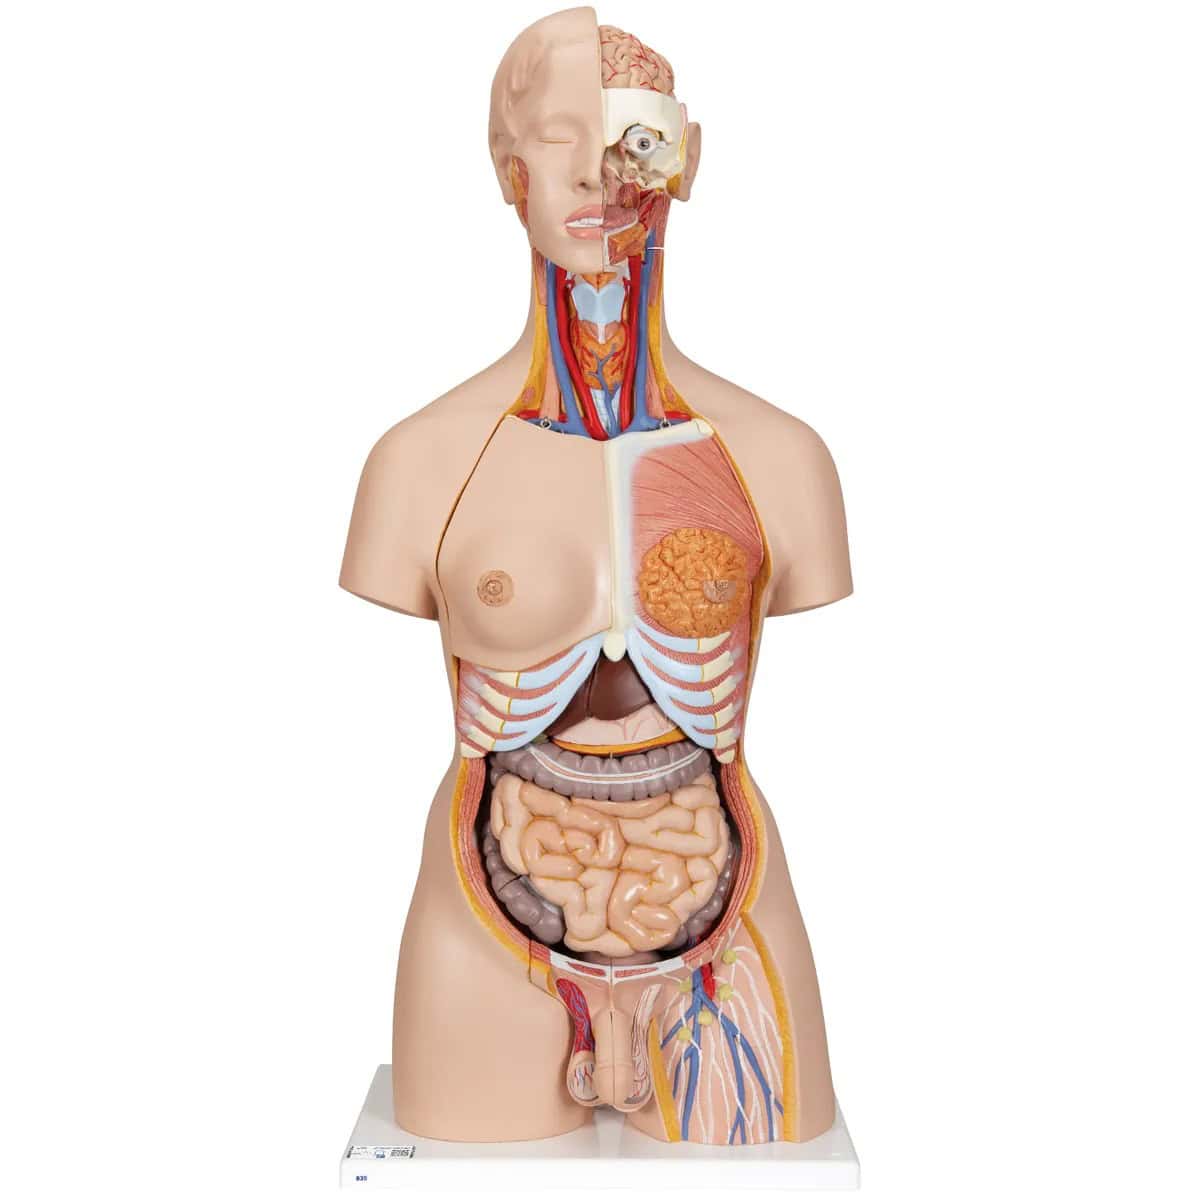

1000200

Torso tweeslachtig met open rug 28-delig